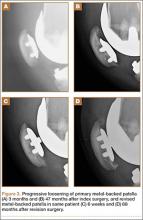

Asymmetric patellae were used in 24 knees, conversion patellae in 64 knees (88 knees total). Forty-nine months after surgery, 1 patella was revised for loosening at its interface with the bone. The 51-year-old active female patient’s asymmetric patella was revised to a conversion patella. The decision to implant another metal-backed device was based on its high density; proper intrusion of acrylic cement would have been questionable. Some early wear was observed on the tibial insert, which was replaced. Sixty-eight months after the revision, the patient was asymptomatic, with a KSS Pain score of 96 and a KSS Function score of 100 (Figure 3). Another revision, for tibial insert exchange only, was performed 48 months after surgery. During this revision, the patella was evaluated and found to be well fixed and functioning normally.